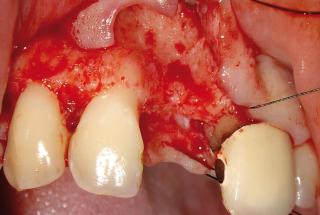

Clinical cases

MPI closely monitors clinical cases in the market to ensure their correct functioning and successful outcome.